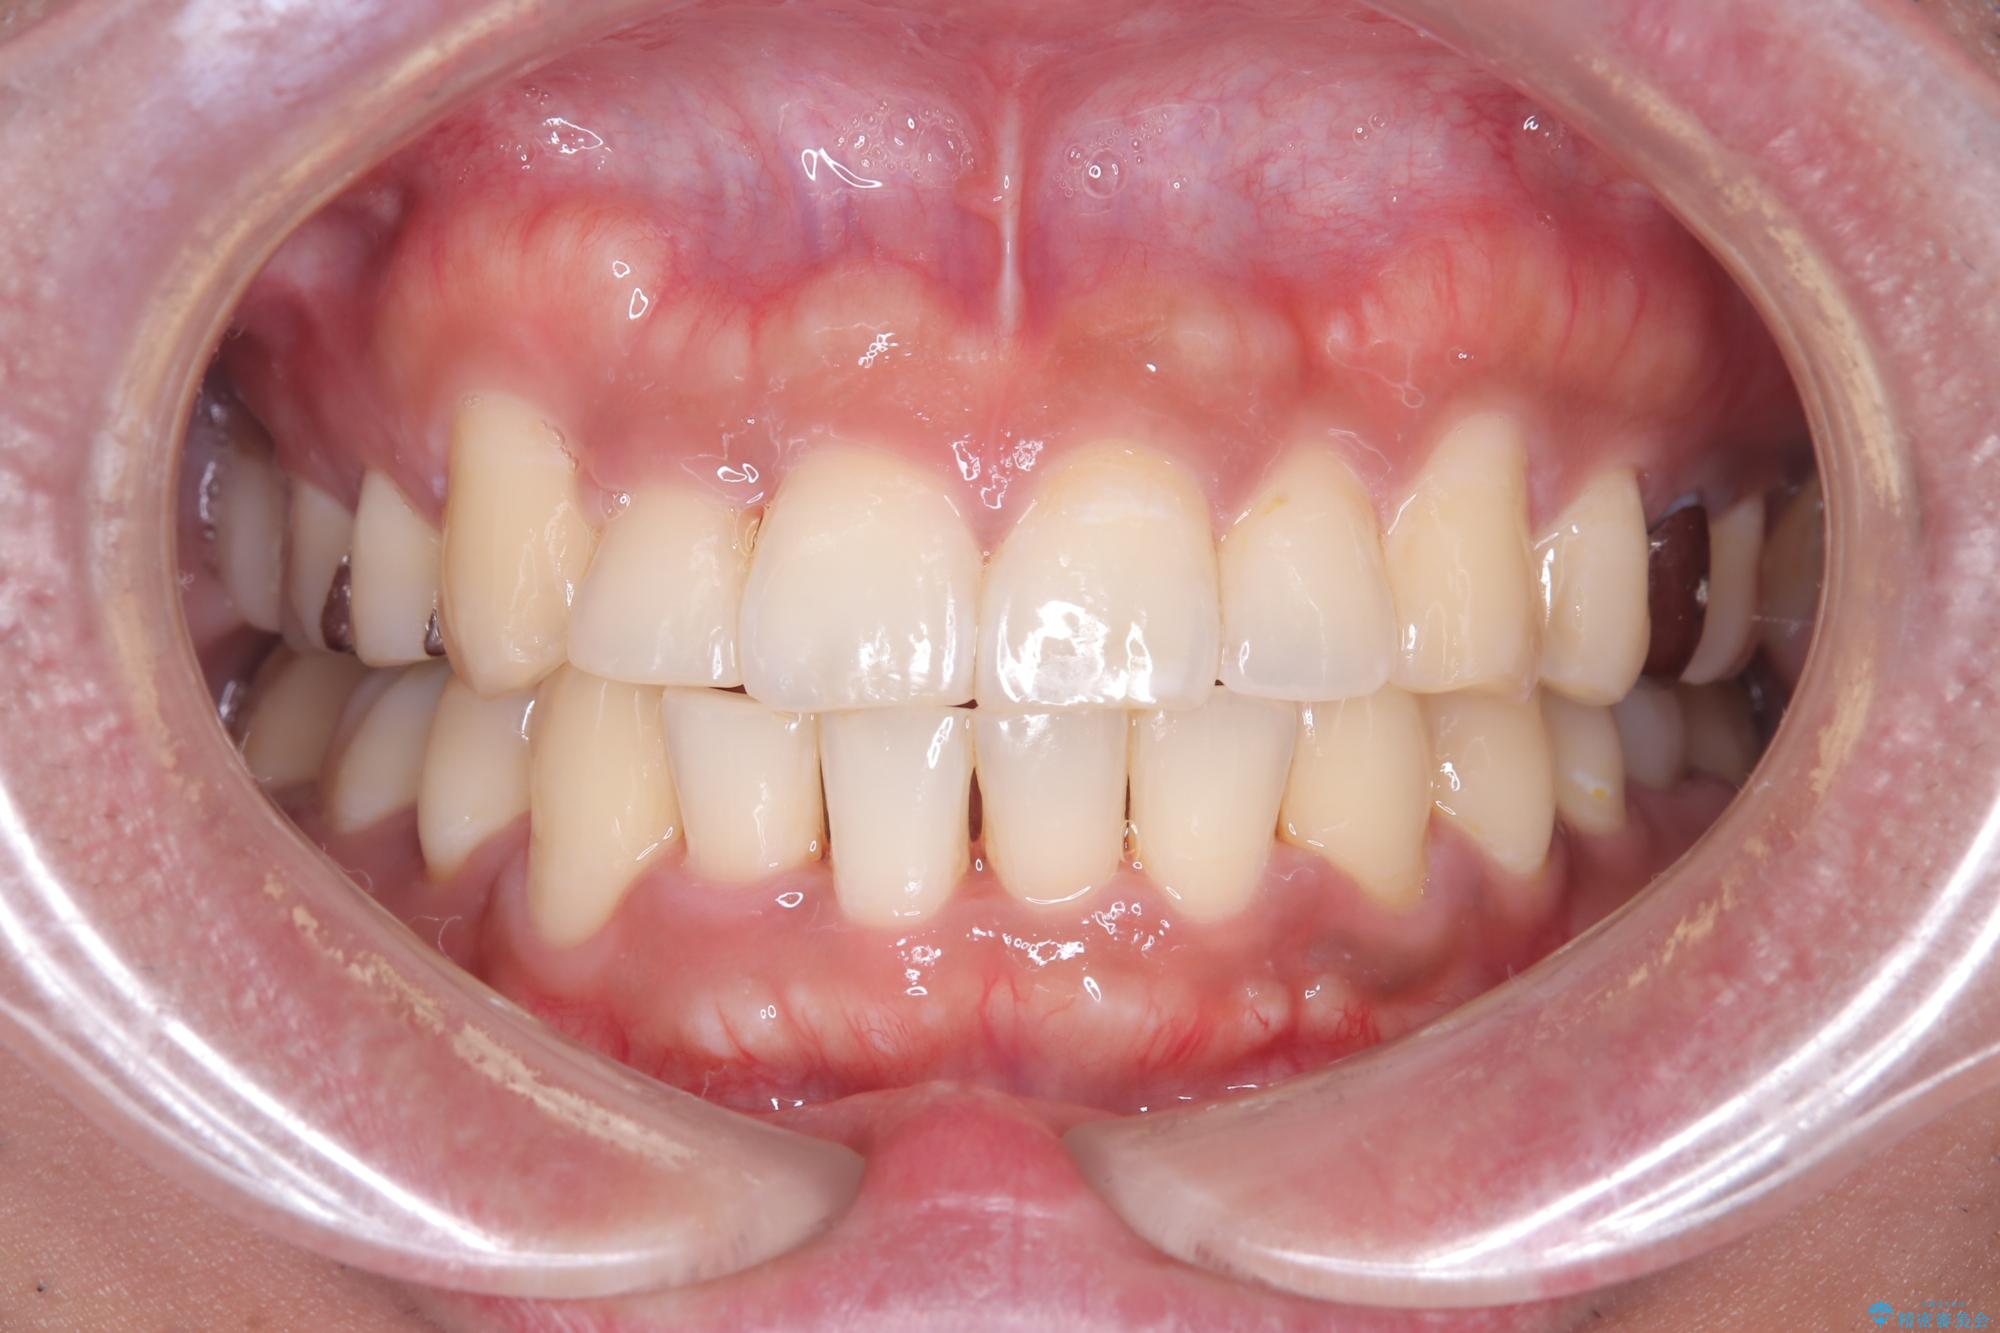

【ワイヤー矯正】八重歯と下の歯の凸凹を治したい

- 主訴:右上の八重歯と、下の歯の凸凹を治したい

上顎右側第一小臼歯と下顎右側第一小臼歯を抜歯しワイヤー矯正を行いました。

右側2級、左側1関係だったため、右側上下第一小臼歯を抜歯し、ワイヤー矯正を行いました。

期間:2年6カ月